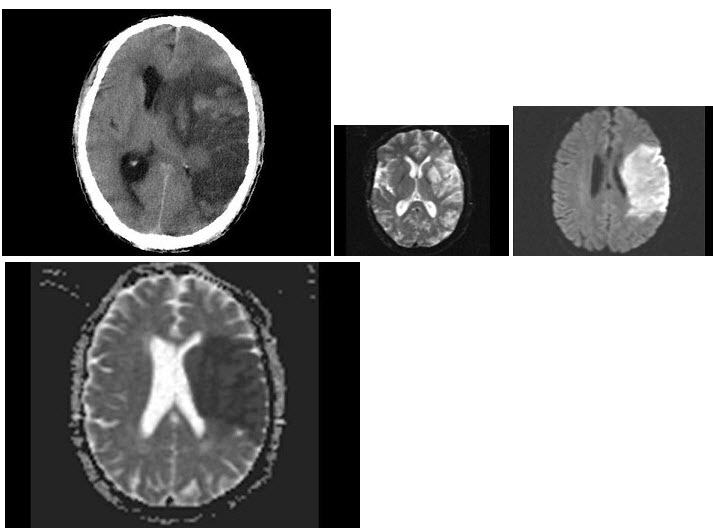

女,75岁,突发左侧肢体无力,嘴角歪斜,言语表达不清,CT如图,最可能的诊断是()

A.右侧颞顶枕叶梗死

B.星形细胞瘤

C.脑脓肿

D.少枝胶质细胞瘤

E.脑囊肿